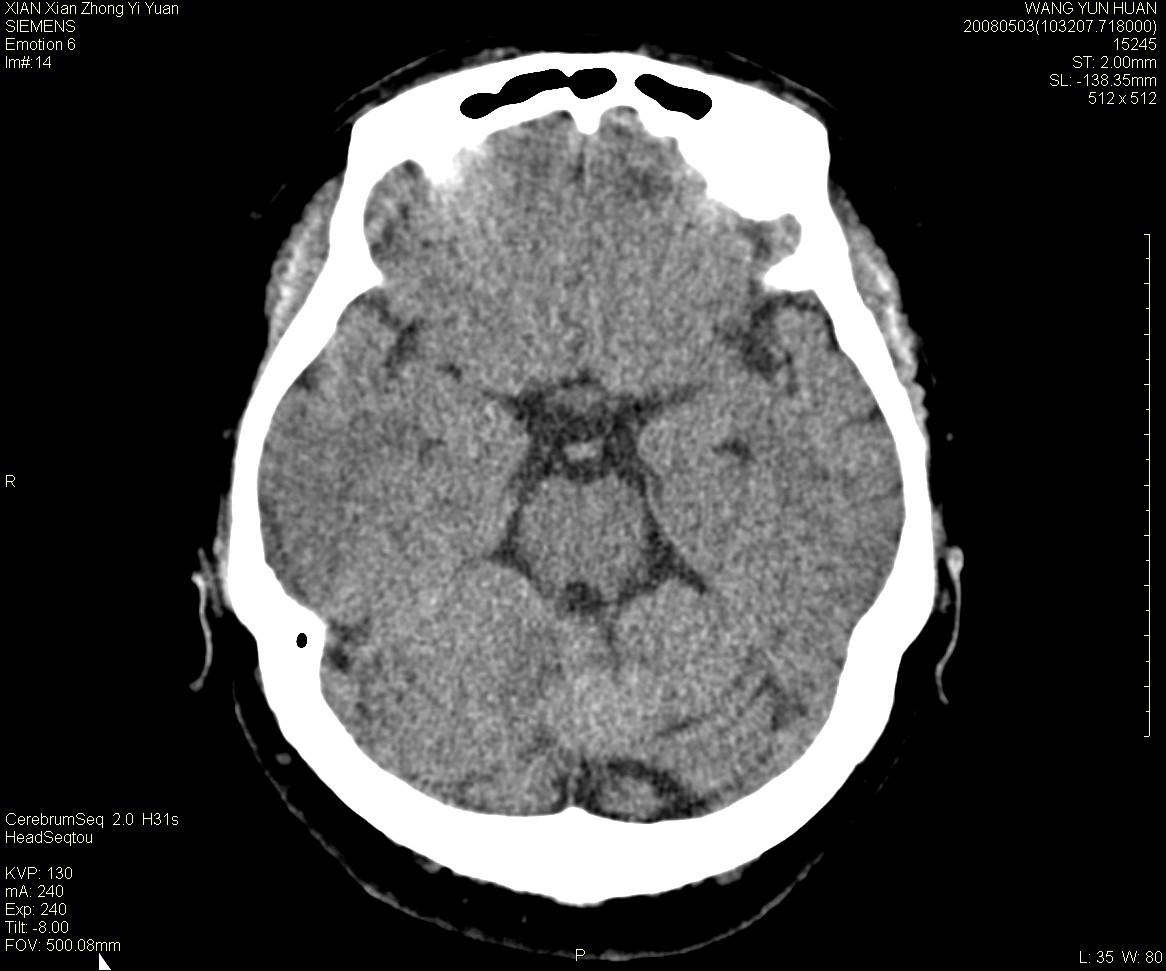

标题: CT13219:(补充强化)请会诊,患者女,60岁,头晕,大家看 [打印本页]

标题: CT13219:(补充强化)请会诊,患者女,60岁,头晕,大家看

病灶显示轻度强化,ct增加4hu左右,大家看是什么肿瘤.

小脑蚓部囊型肿块,内有实性结节及钙化点。增强后囊壁及结节轻度强化。

考虑蚓部星形细胞瘤(ⅱ级可能性大)。

小脑蚓部肿块,周围无明显占位效应及水肿带,增强轻度强化,考虑低分级星形细胞瘤。